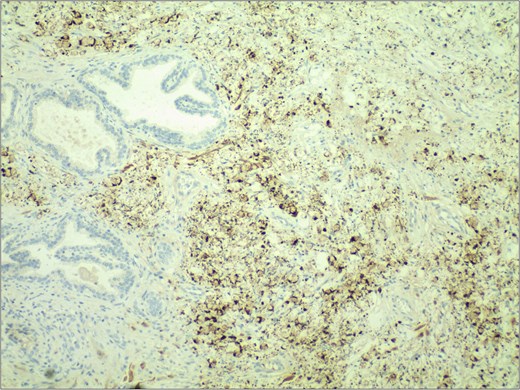

In November 2024, the patient presented with progressive dysuria for 3 years, accompanied by recurrent urinary retention for 3 weeks. Physical examination revealed a prostate enlarged to grade II, with a firm texture, smooth surface, no palpable nodules, no tenderness, a shallow median sulcus, and no sphincter relaxation. Imaging studies with 3.0 T prostate magnetic resonance imaging (MRI) showed a prostate measuring ⁓5.7 × 4.8 × 5.7 cm, with marked enlargement of the transition zone and heterogeneous signals. Small, patchy short T2 signals were internally observed, along with slightly high diffusion-weighted imaging (DWI) signals and slightly decreased apparent diffusion coefficient (ADC) signals, yielding a PI-RADS score of 3. The peripheral zone was thinned and indistinct. The seminal vesicles showed normal size and morphology, and the bladder-seminal vesicle triangle was intact. No enlarged lymph nodes were evident in the pelvic cavity. Laboratory tests showed a total prostate-specific antigen level of 1.759 ng/ml. Initially diagnosed with benign prostatic hyperplasia, the patient underwent transurethral enucleation of the prostate with a thulium laser under general anesthesia on 19 November 2024. The surgery was successful. Postoperative pathology indicated poorly differentiated adenocarcinoma, predominantly signet ring cell carcinoma, presumed to be of gastric origin (Fig. 1). Immunohistochemical analysis revealed negativity for prostate cancer markers (PSA and P504S) and positivity for gastrointestinal tumor markers [CKP(3+), CK20(+), CEA(3+), Villin(2+), CDX-2(2+)] (Fig. 2). Morphological comparison with previous gastric cancer pathology slides showed similar features, confirming metastatic gastric signet ring cell carcinoma to the prostate. The patient continued chemotherapy with the original gastric cancer regimen postoperatively and is currently under follow-up.

Histopathological examination revealed extensive infiltration of signet-ring cells, with the cytoplasm filled with mucinous vacuoles, and the nuclei showing eccentric positioning and dark staining. H&E stain 40×.